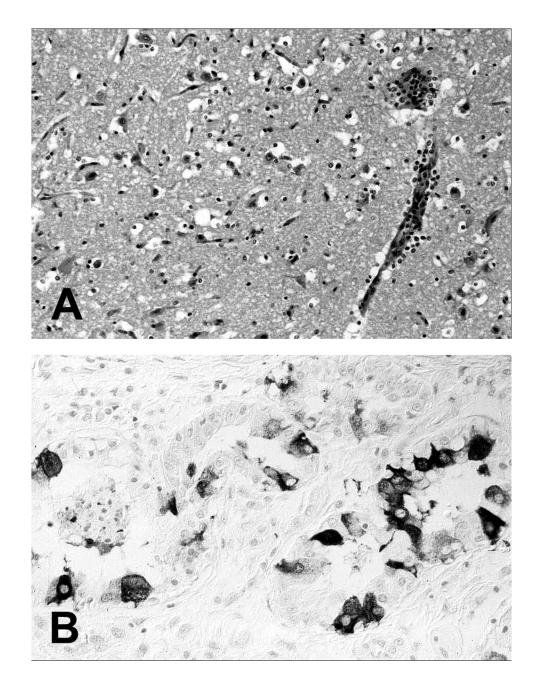

Approximately 21,700 seals died during a morbillivirus epidemic in northwestern Europe in 2002. Phocine distemper virus 1 was isolated from seals in German waters. The sequence of the P gene showed 97% identity with the Dutch virus isolated in 1988. There was 100% identity with the Dutch isolate from 2002 and a single nucleotide mismatch with the Danish isolate.